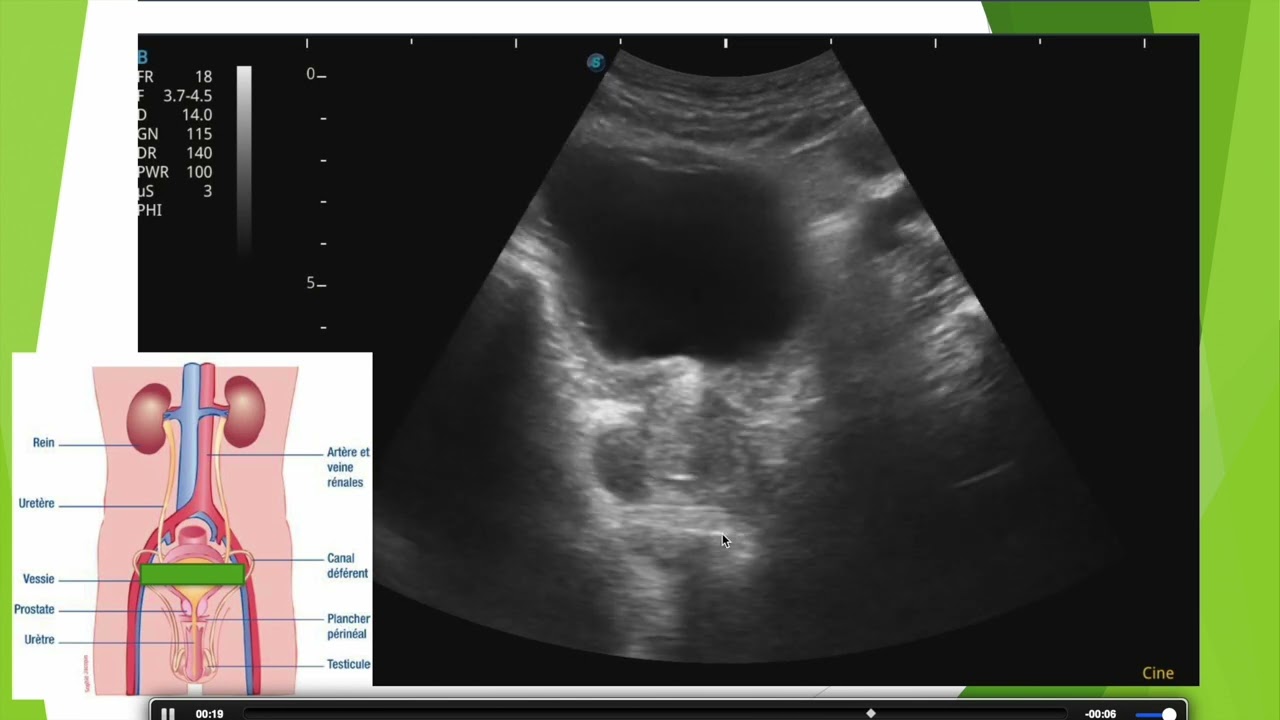

Cancer de prostate en échographie

Découverte d'un cancer de prostate métastasé en échographie. Aspect de la prostate et de la vessie en échographie suspubienne et exploration d'une tumeur inguinale gauche.